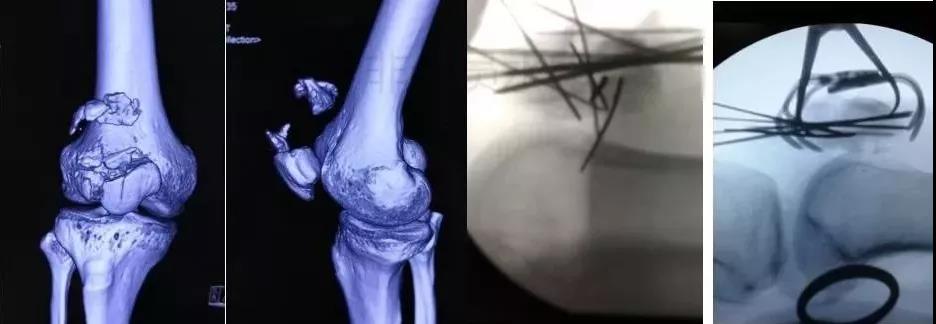

5)胫骨近端骨折(平台)

- 确定损伤机制,暴力损伤程度。

- 排除骨筋膜室综合征及血管,神经损伤。

- 高能量损伤,皮肤软组织条件差的,应延期手术。